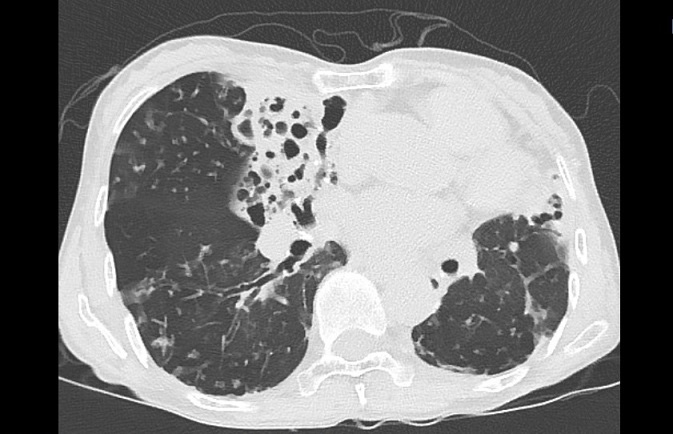

비결핵항산균에 감염된 폐사진